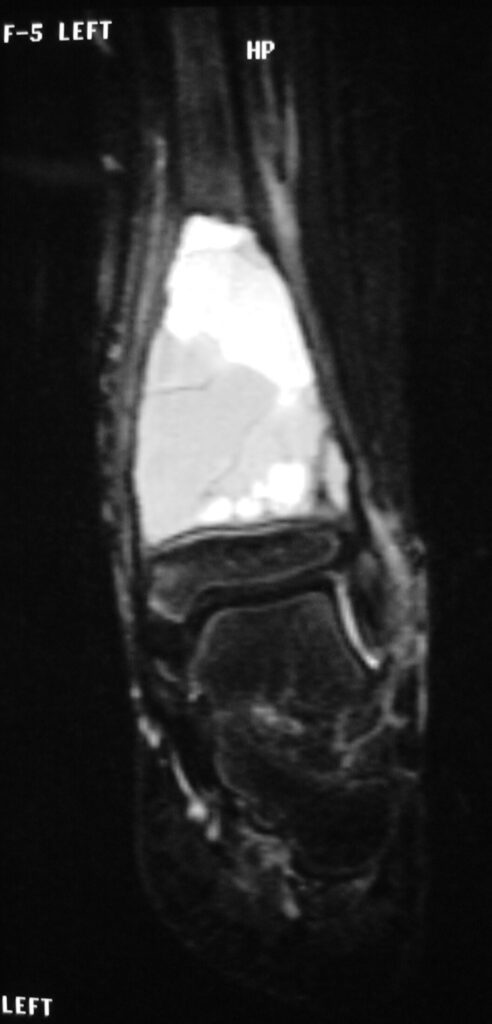

Fig 2 a-e. MRI of an ABC of Distal Tibia: Fig 2 a-c: geographic cystic expansile lesion with fluid-fluid levels. The fluid-fluid levels are caused by bleeding into the cavities. The blood collects and the degredation products settle to the gravity dependent areas of the cavities. This shows up as fluid-fluid levels on the MRI. Fig 2 d,e: This is a gadolinium enhanced MRI of the ABC of the distal tibia. There is peripheral and septal enhancement indication cyst formation. The contrast outlines the cystic cavities but does not enter into the center

Fig 2 a: Coronal T2 weighted MRI of an ABC

MRI

- Geographic well circumscribed

- High signal on T2 weighted MRI images

- Fluid/Fluid level (T2) are highly characteristic